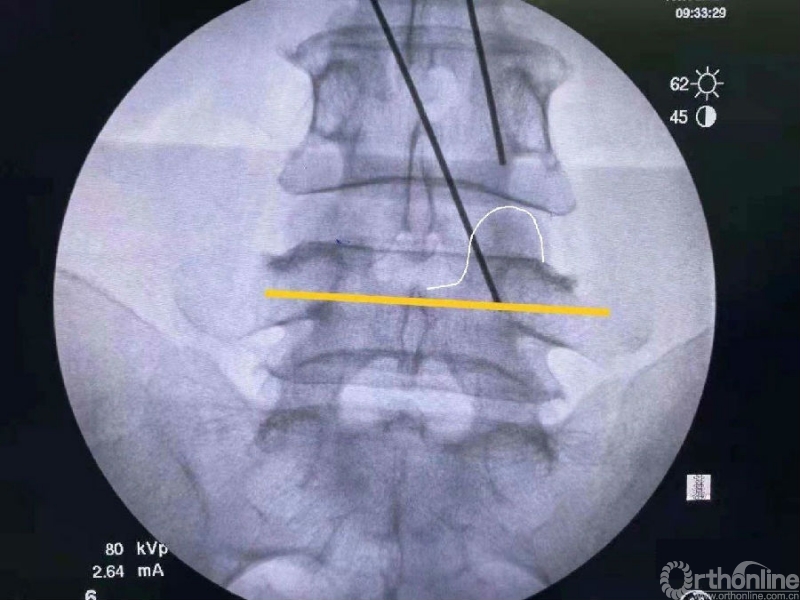

我们选用mark磨钻在下关节突上钻孔固定进行透视来确定关节突内缘磨除的外界。

定位磨钻细小,且可立于钻孔内进行透视定位。

术前克氏针确定内镜口位置位于椎板稍微偏远,是一个比较理想的定位。